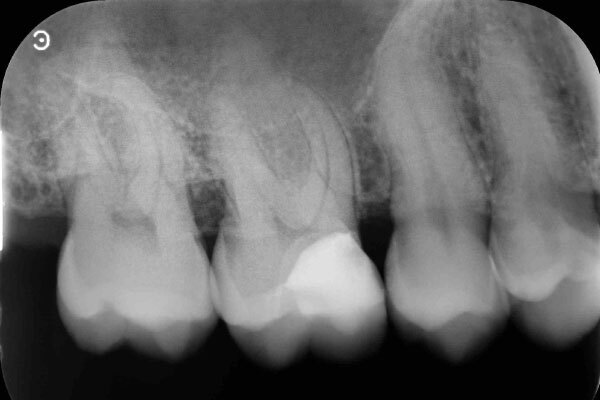

術前のデンタルX線写真と口腔内写真です。左下の一番奥の歯(#37)です。

左下の親知らずは1ヵ月ほど前に抜いたそうです。

親知らずと隣り合っていた歯の後ろ側(遠心)から虫歯が進行しています。

術後デンタルX線写真

この状態で1ヵ月から3か月ほど経過を診させていただき、神経に問題が起きないかどうか確認します。